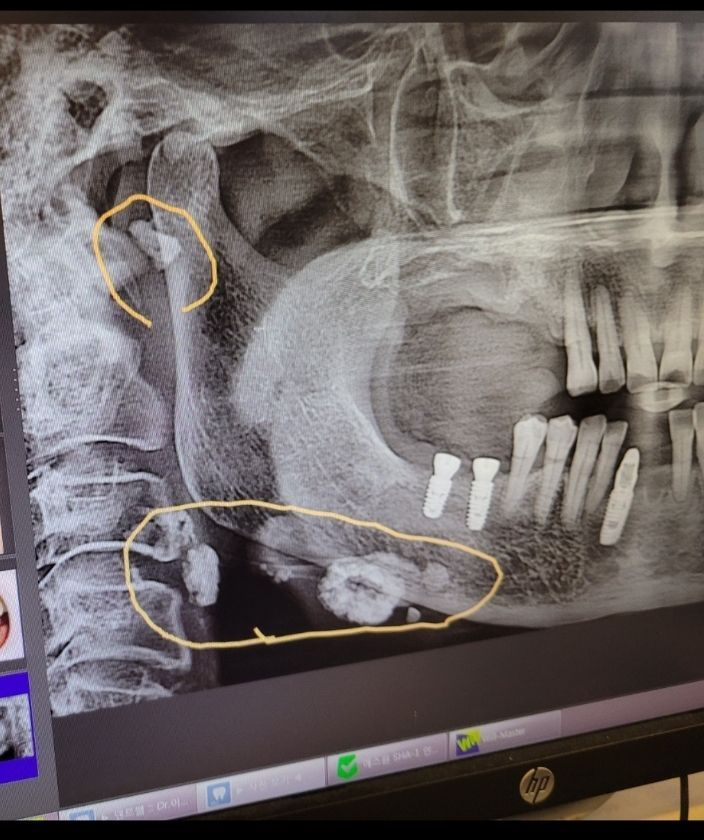

치과에 어머님을 모시고갔는데 동그라미체크부분

목에머가 있다고 이빈후과를 가라는데

둥근 구조물에 석회화된 모습이 보입니다. 침샘이나 림프절에 만성적인 염증반응 등의 원인으로 석회화가 진행되었을 것이라 추정됩니다. 모습이 양성의 병변일 것이라 추정되지만 이비인후과 전문의에게 확인을 받으시는 것이 가장 정확하고 안전합니다.

침을 생성하는 이하선의 염증 또는 석회화

또는 임파선의 염증이나 석회화일수 있습니다.

드물게는 암일수도 있습니다.